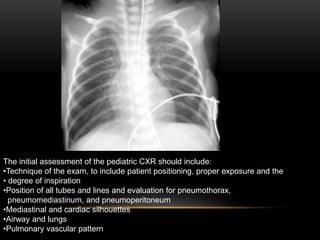

Indications For Chest X Rays In Children And How To Obtain And Interpret Them